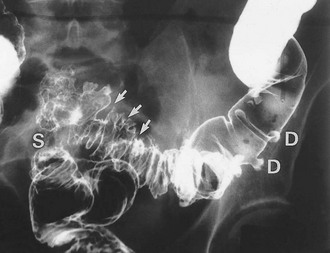

Diverticular disease occasionally presents with large bowel obstruction due to acute inflammatory thickening, muscle hypertrophy and spasm. Incomplete obstruction is more common and presents as severe constipation. Chronic diverticular inflammation sometimes causes local fibrous strictures, particularly in the sigmoid, which cause intermittent bouts of constipation when the stool is dry. When detected radiologically or endoscopically, these strictures must be distinguished from malignancy or Crohn's disease by biopsy (Figs. 29.5 and 29.7).

Pericolic abscess represents a further extension of the pathological process just described. The clinical presentation is similar at first but fails to resolve with antibiotics. The patient suffers persistent pain and tenderness, a swinging pyrexia and incomplete obstruction due to spasm of bowel wall muscle. Sometimes a pericolic abscess presents as ‘pyrexia of unknown origin’ or even systemic sepsis (septicaemia). A pericolic abscess may drain spontaneously into bowel, producing an attack of purulent diarrhoea; the condition then resolves. Diagnosis of a pericolic abscess is made on CT scan. A contrast enema may show leakage of contrast into the abscess cavity (see Fig. 29.5).